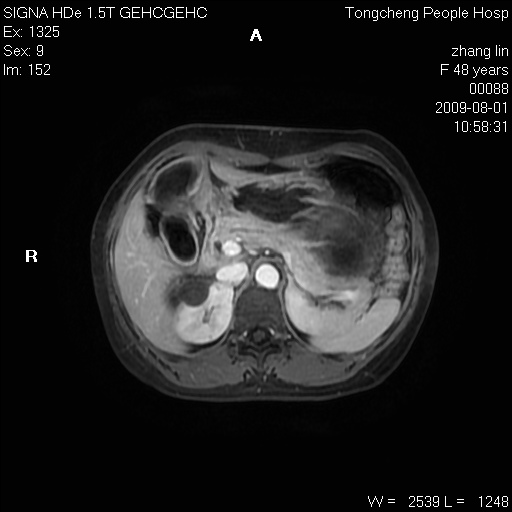

女,48岁。健康体检,彩超发现右肾占位性病变。平素健康。

临床诊断:右肾占位性病变,性质待定(囊肿?肿瘤?)。

上中腹部mr平扫+增强扫描,图像如下:

右肾上极见一类圆形病灶,t1wi呈等信号t2wi呈等高混杂信号,三期增强无强化,边界清---考虑囊肿出血。

同反相位均表现为等信号,病变无强化,考虑含蛋白的囊肿可能,弥散加权相或许有些帮助,

肝囊肿

慢性胆囊炎